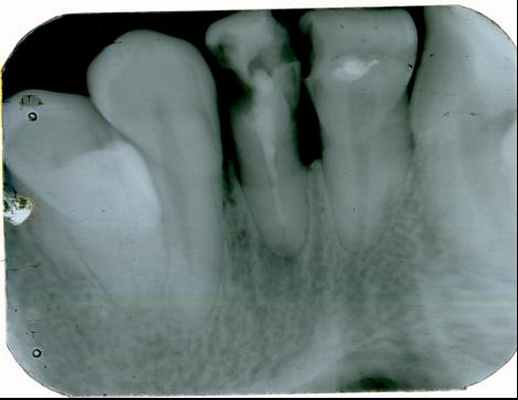

Прямые панорамные рентгенограммы имеют преимущество перед внутриротовыми снимками по богатству деталями изображения костной ткани и твердых тканей зубов. При минимальной лучевой нагрузке они позволяют получить широкий обзор альвеолярного отростка и зубного ряда, облегчают работу рентгенолаборанта и резко сокращают время исследования. На этих снимках хорошо видны полости зуба, корневые каналы, периодонтальные щели, межальвеолярные гребни и костная структура не только альвеолярных отростков, но и тел челюстей. На панорамных рентгенограммах выявляются альвеолярная бухта и нижняя стенка верхнечелюстной пазухи, нижнечелюстной канал и основание нижнечелюстной кости.

На основании панорамных снимков диагностируют кариес и его осложнения, кисты разных типов, новообразования, повреждения челюстных костей и зубов, воспалительные и системные поражения. У детей хорошо определяется состояние и положение зачатков зубов.

Особенно важно использовать ортопантомографию в детской стоматологии, где она не имеет конкурентов в связи с низкими дозами облучения и большим объемом получаемой информации. В детской практике ортопантомография помогает диагностировать переломы, опухоли, остеомиелит, кариес, периодонтиты, кисты, определять особенности прорезывания зубов и положение зачатков.